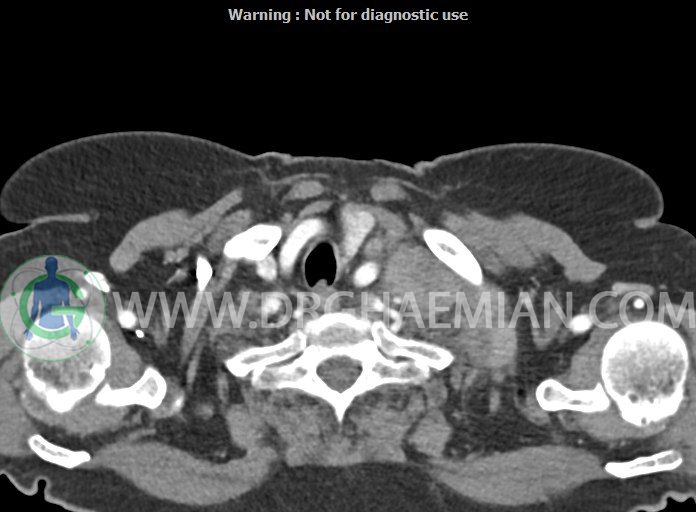

در سی تی اسکن اسپیرال از گردن با تزریق (مولتی دیدکتور 16 با مقاطع ظریف و بازسازی های ساژیتال و کرونال):

– تصویر توه های نسج نرمی oval shape متعدد با Enhancement تقریباً هوموژن، قرار گرفته در سمت چپ گردن، در لول غضروف کریکوئید با اثر فشاری شدید و compression ورید ژوگولار، با گسترش تحتانی به اینفراکلاویکولار چپ، به حداکثر ابعاد 28x50mm (با Enhancement مختصر هتروژن در این توده)

در درجه اول مطرح کننده لنفادنوپاتی متاستاتیک مطرح می باشد بالین، تومورهای منشأ گرفته از غلاف عصبی زنحیره سمپاتیک چپ گردنی، شبکه براکیال و لنفوم نیز در DDX قرار دارند. لذا نمونه برداری بافتی جهت بررسی بیشتر توصیه می شود.

– اسکولیوز مهره های سرویکال با تحدب به راست، احتمالاً در زمینه اثر فشاری توده های مذکور

مشهود است.